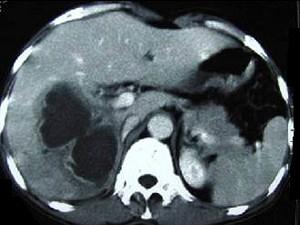

问题 男,45岁,右上腹痛,有发热,白细胞计数升高,CT检查如图,最可能诊断是 ( )

选项 A、肝黄色肉芽肿 B、肝转移癌 C、肝包虫病 D、肝脓肿 E、原发性肝癌

答案 D